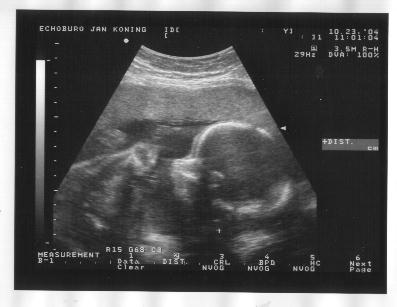

23 oktober 2004

Zijaanzicht hoofd, handje bij het gezicht en oog, bovenste helft borst, opgetrokken knietjes